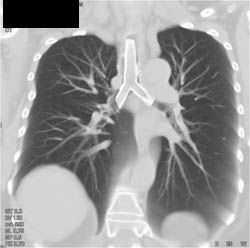

Stent in Airway With Granulomatous Tissue Pushing on Right Side of Trachea at Bifurcation- Various Renderings